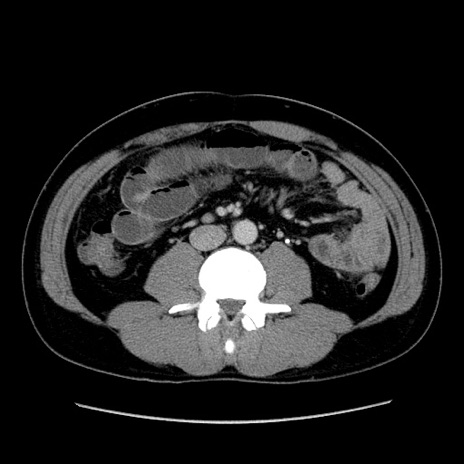

冠状断像

【症例】30歳代男性

【主訴】腹痛、嘔吐

【現病歴】昨晩から突然の腹痛あり、その後嘔吐、軟便も出現。腹痛が改善しないため救急搬送となる。2日前にしめ鯖の食事歴あり。

【身体所見】意識清明、苦悶様、BP 135/90mmHg、BT 35.7℃、腹部:平坦、やや硬、心窩部〜臍部に自発痛、圧痛あり、筋性防御+、反跳痛-

【データ】WBC 8100、CRP 0.57